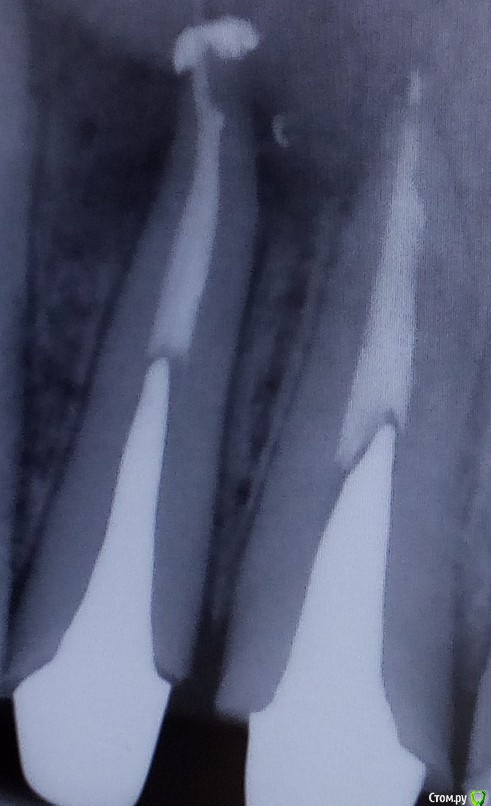

Shelly2000 Опубликовано 10 июля, 2017 Поделиться Опубликовано 10 июля, 2017 Уважаемые специалисты! Помогите, пожалуйста, понять, что изображено на снимках.Было лечение кисты зуба 12, потом пломбирование каналов 12 и 11, потом установлена вкладок в оба зуба.На первом контрольном снимке в момент пломбирования и на втором снимке в момент примерки вкладок около верхушки корня зуба 12 наблюдается нечто инородное.По яркости от пломбировочного материала отличается. Плюс видно перемещение относительно зуба и небольшое изменение формы. Разница по времени между снимками - чуть больше месяца.Что это может быть? Насколько опасно? Ссылка на комментарий

St. Опубликовано 10 июля, 2017 Поделиться Опубликовано 10 июля, 2017 Ничего критичного не увидела.скорее всего пломбирования материал. Наблюдайте. Через 6 и 12 мес нужно будет сделать контрольные снимки. Ссылка на комментарий

dok1 Опубликовано 11 июля, 2017 Поделиться Опубликовано 11 июля, 2017 Милионы людей ходят с подобными артефактами и ничего. Да, конечно, хочется идеальную картинку с пломбировочным материалом в пределах корня. Но современные материалы не раздражают ткани за пределами корня так, как это делают старые, отжившие своё цементы и пасты. А иногда выведение малого количества лечебной пасты заложено технологией лечения. Так что всё у вас в пределах нормы. 2 Ссылка на комментарий

AndyAndy Опубликовано 11 июля, 2017 Поделиться Опубликовано 11 июля, 2017 Я вижу значительное уменьшение воспалительного процесса на верхушке корня. Так что я бы на вашем месте радовался, и забил бы на выведенный материал Ссылка на комментарий